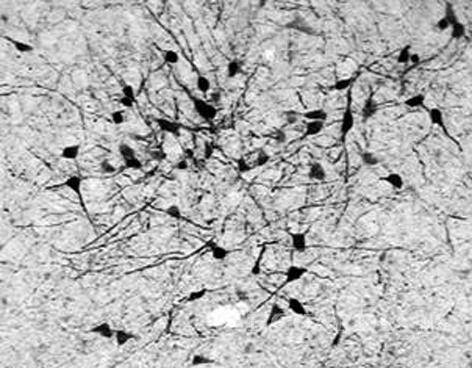

Científicos del Karolinska Institutet, dependencia que otorga los Premios Nobel de ciencia, han identificado un nuevo grupo de células nerviosas en el cerebro, las cuales son responsables de regular las funciones cardiovasculares, lo que podría dar nuevas herramientas para tratar este tipo de enfermedades.

El estudio, elaborado con ratones, permitió detectar este tipo de neuronas que se desarrollan gracias a la intervención de la hormona tiroidea, la cual se expresa en las glándula tiroides, de acuerdo a un comunicado del instituto.